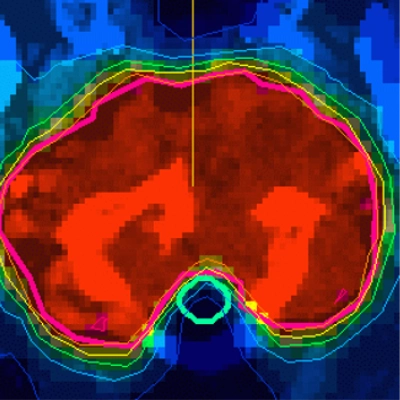

- PHSP - Phase-space database for external beam radiotherapy

- Positron Emitters - Cross sections for production of PET emitters

- Therapeutic isotopes - Cross section for production of therapeutic radionuclides